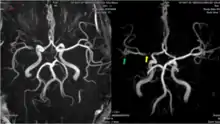

![]() Arterial supply of the brain | |

The leptomeningeal collateral circulation (also known as leptomeningeal anastomoses or pial collaterals) is a network of small blood vessels in the brain that connects branches of the middle, anterior and posterior cerebral arteries (MCA, ACA, and PCA),[1] with variation in its precise anatomy between individuals.[2] During a stroke, leptomeningeal collateral vessels allow limited blood flow when other, larger blood vessels provide inadequate blood supply to a part of the brain.[3]

Inter-territorial end to end anastomoses exist between branches of the anterior cerebral artery and middle cerebral artery, the posterior cerebral artery and middle cerebral artery, the anterior cerebral artery and posterior cerebral artery, and the right and left anterior cerebral arteries.[7][8][9][10] Intra-territorial anastamoses connect adjacent arterial branches within the same arterial territory (between two branches of the same middle cerebral artery, for example).[5]